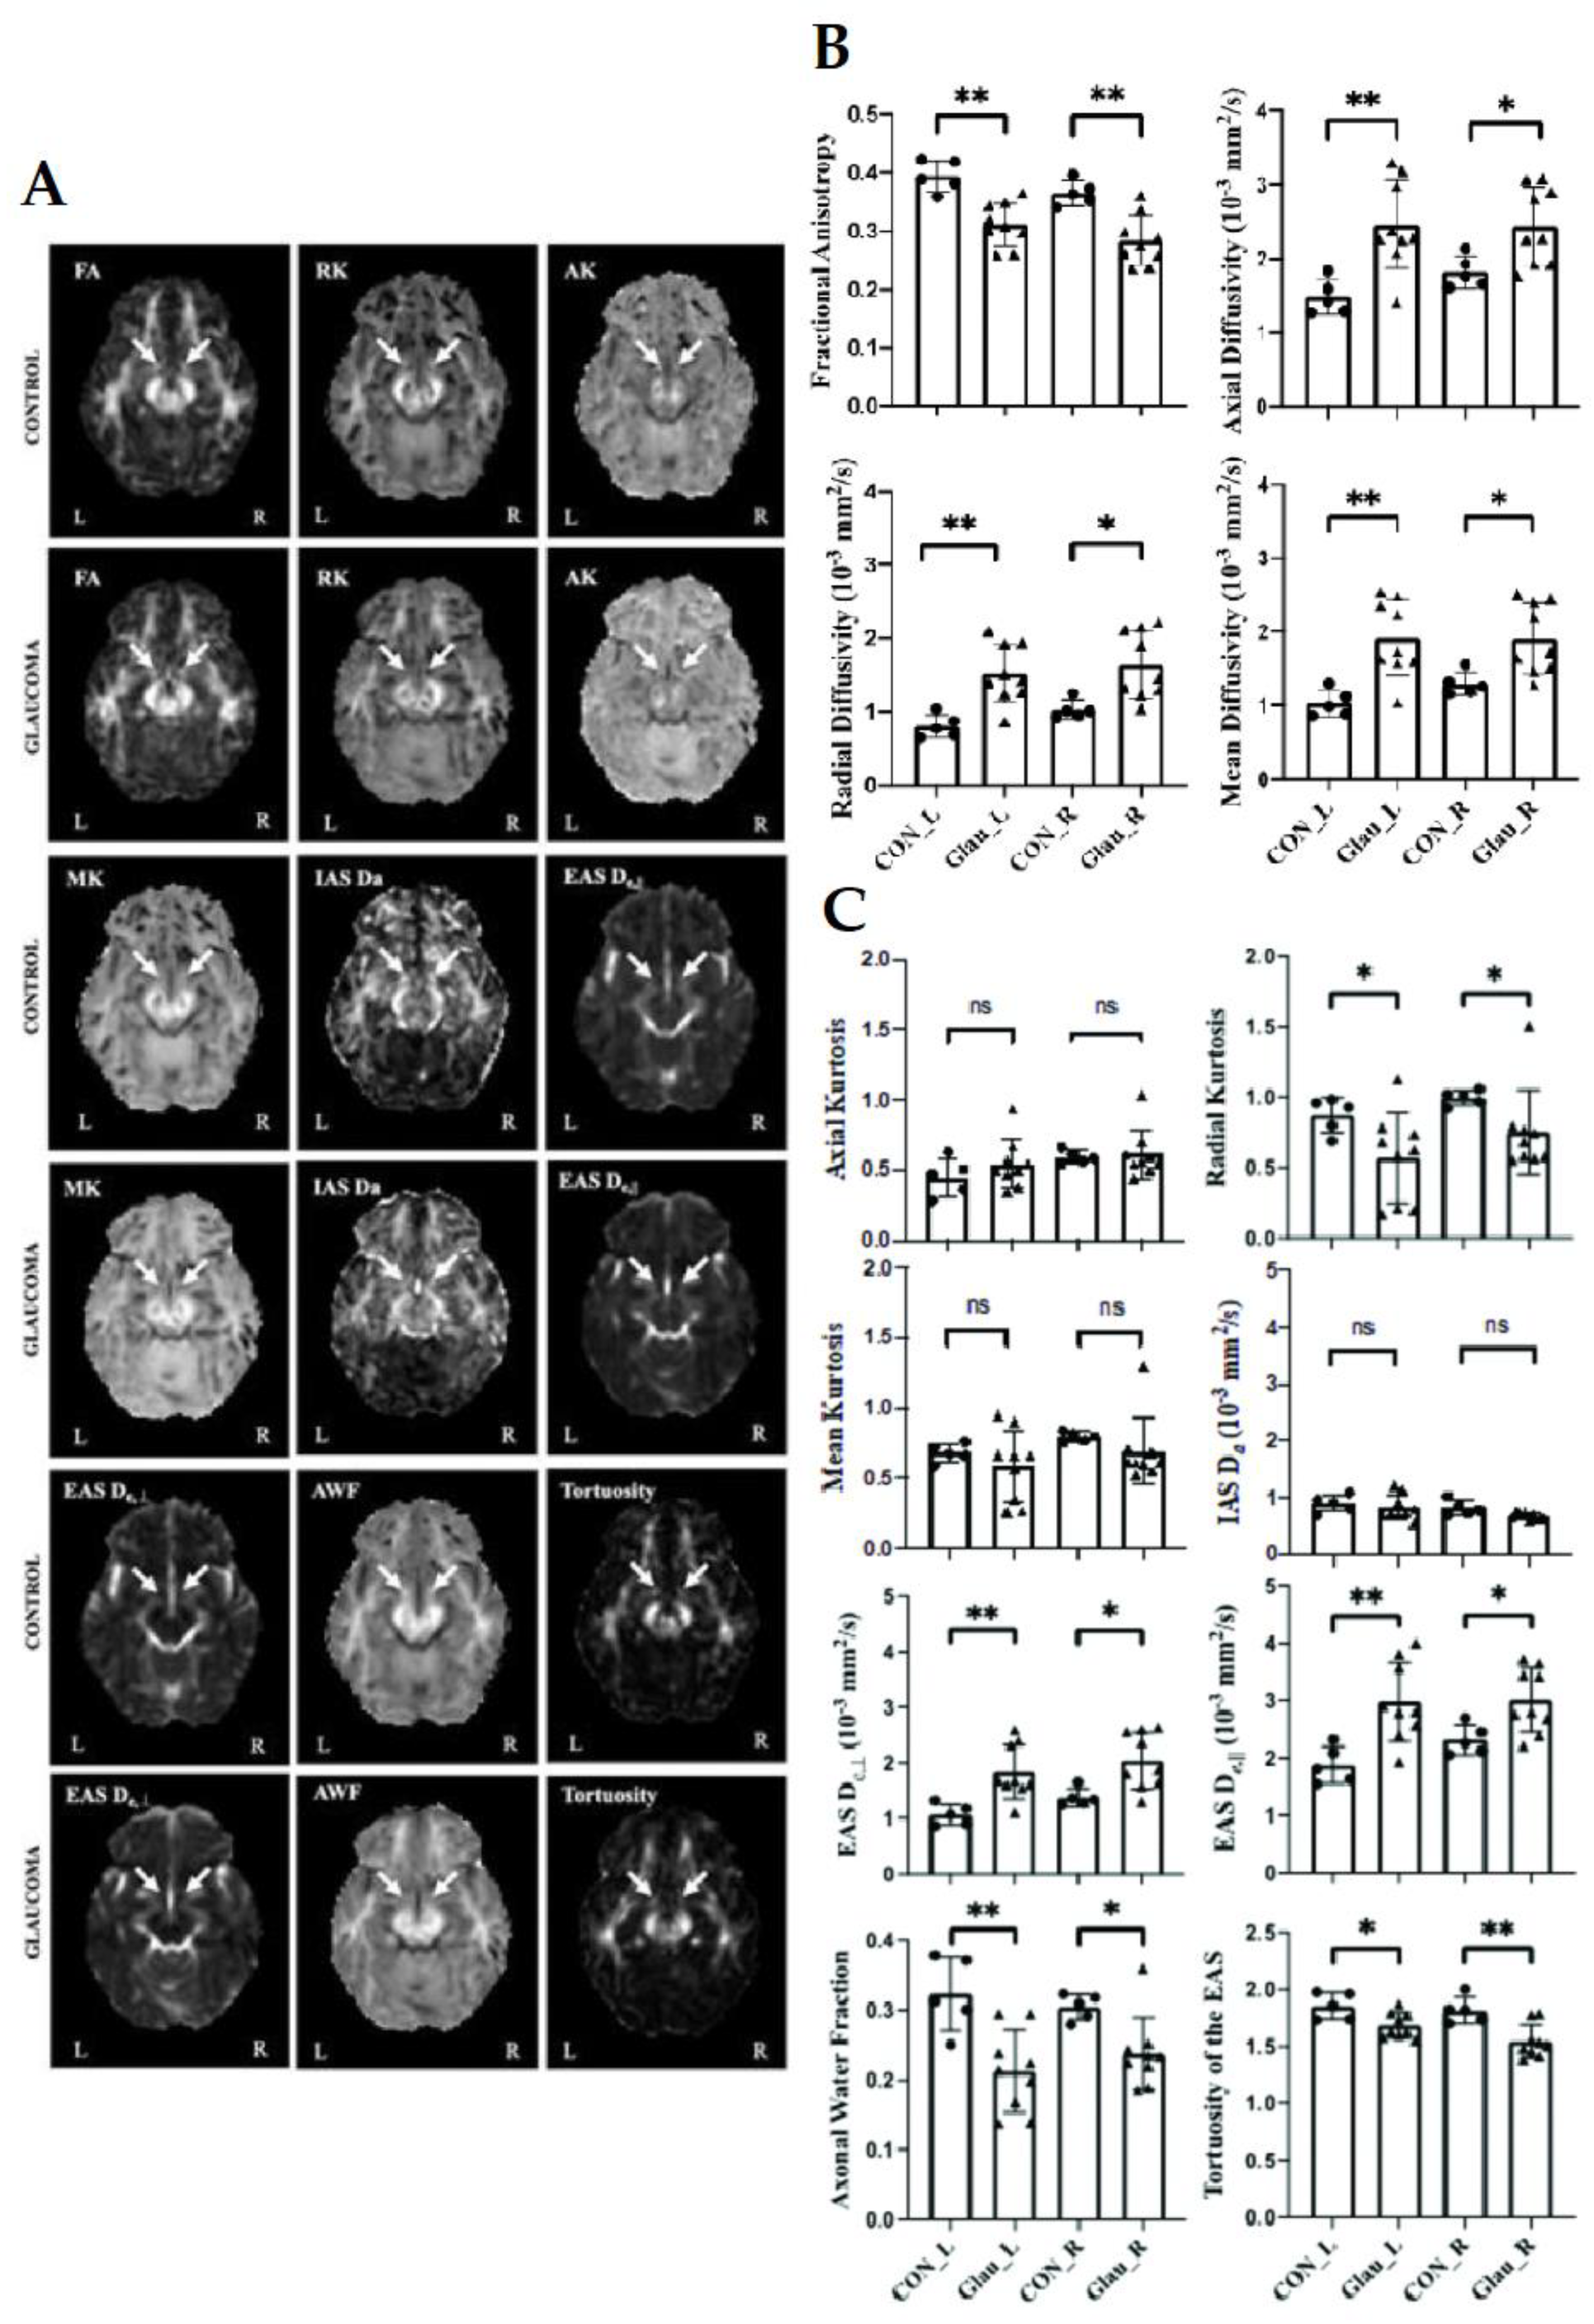

2.5. Diffusion Kurtosis Imaging (DKI) in Glaucoma

2.6. White Matter Tract Integrity (WMTI) Model in Glaucoma